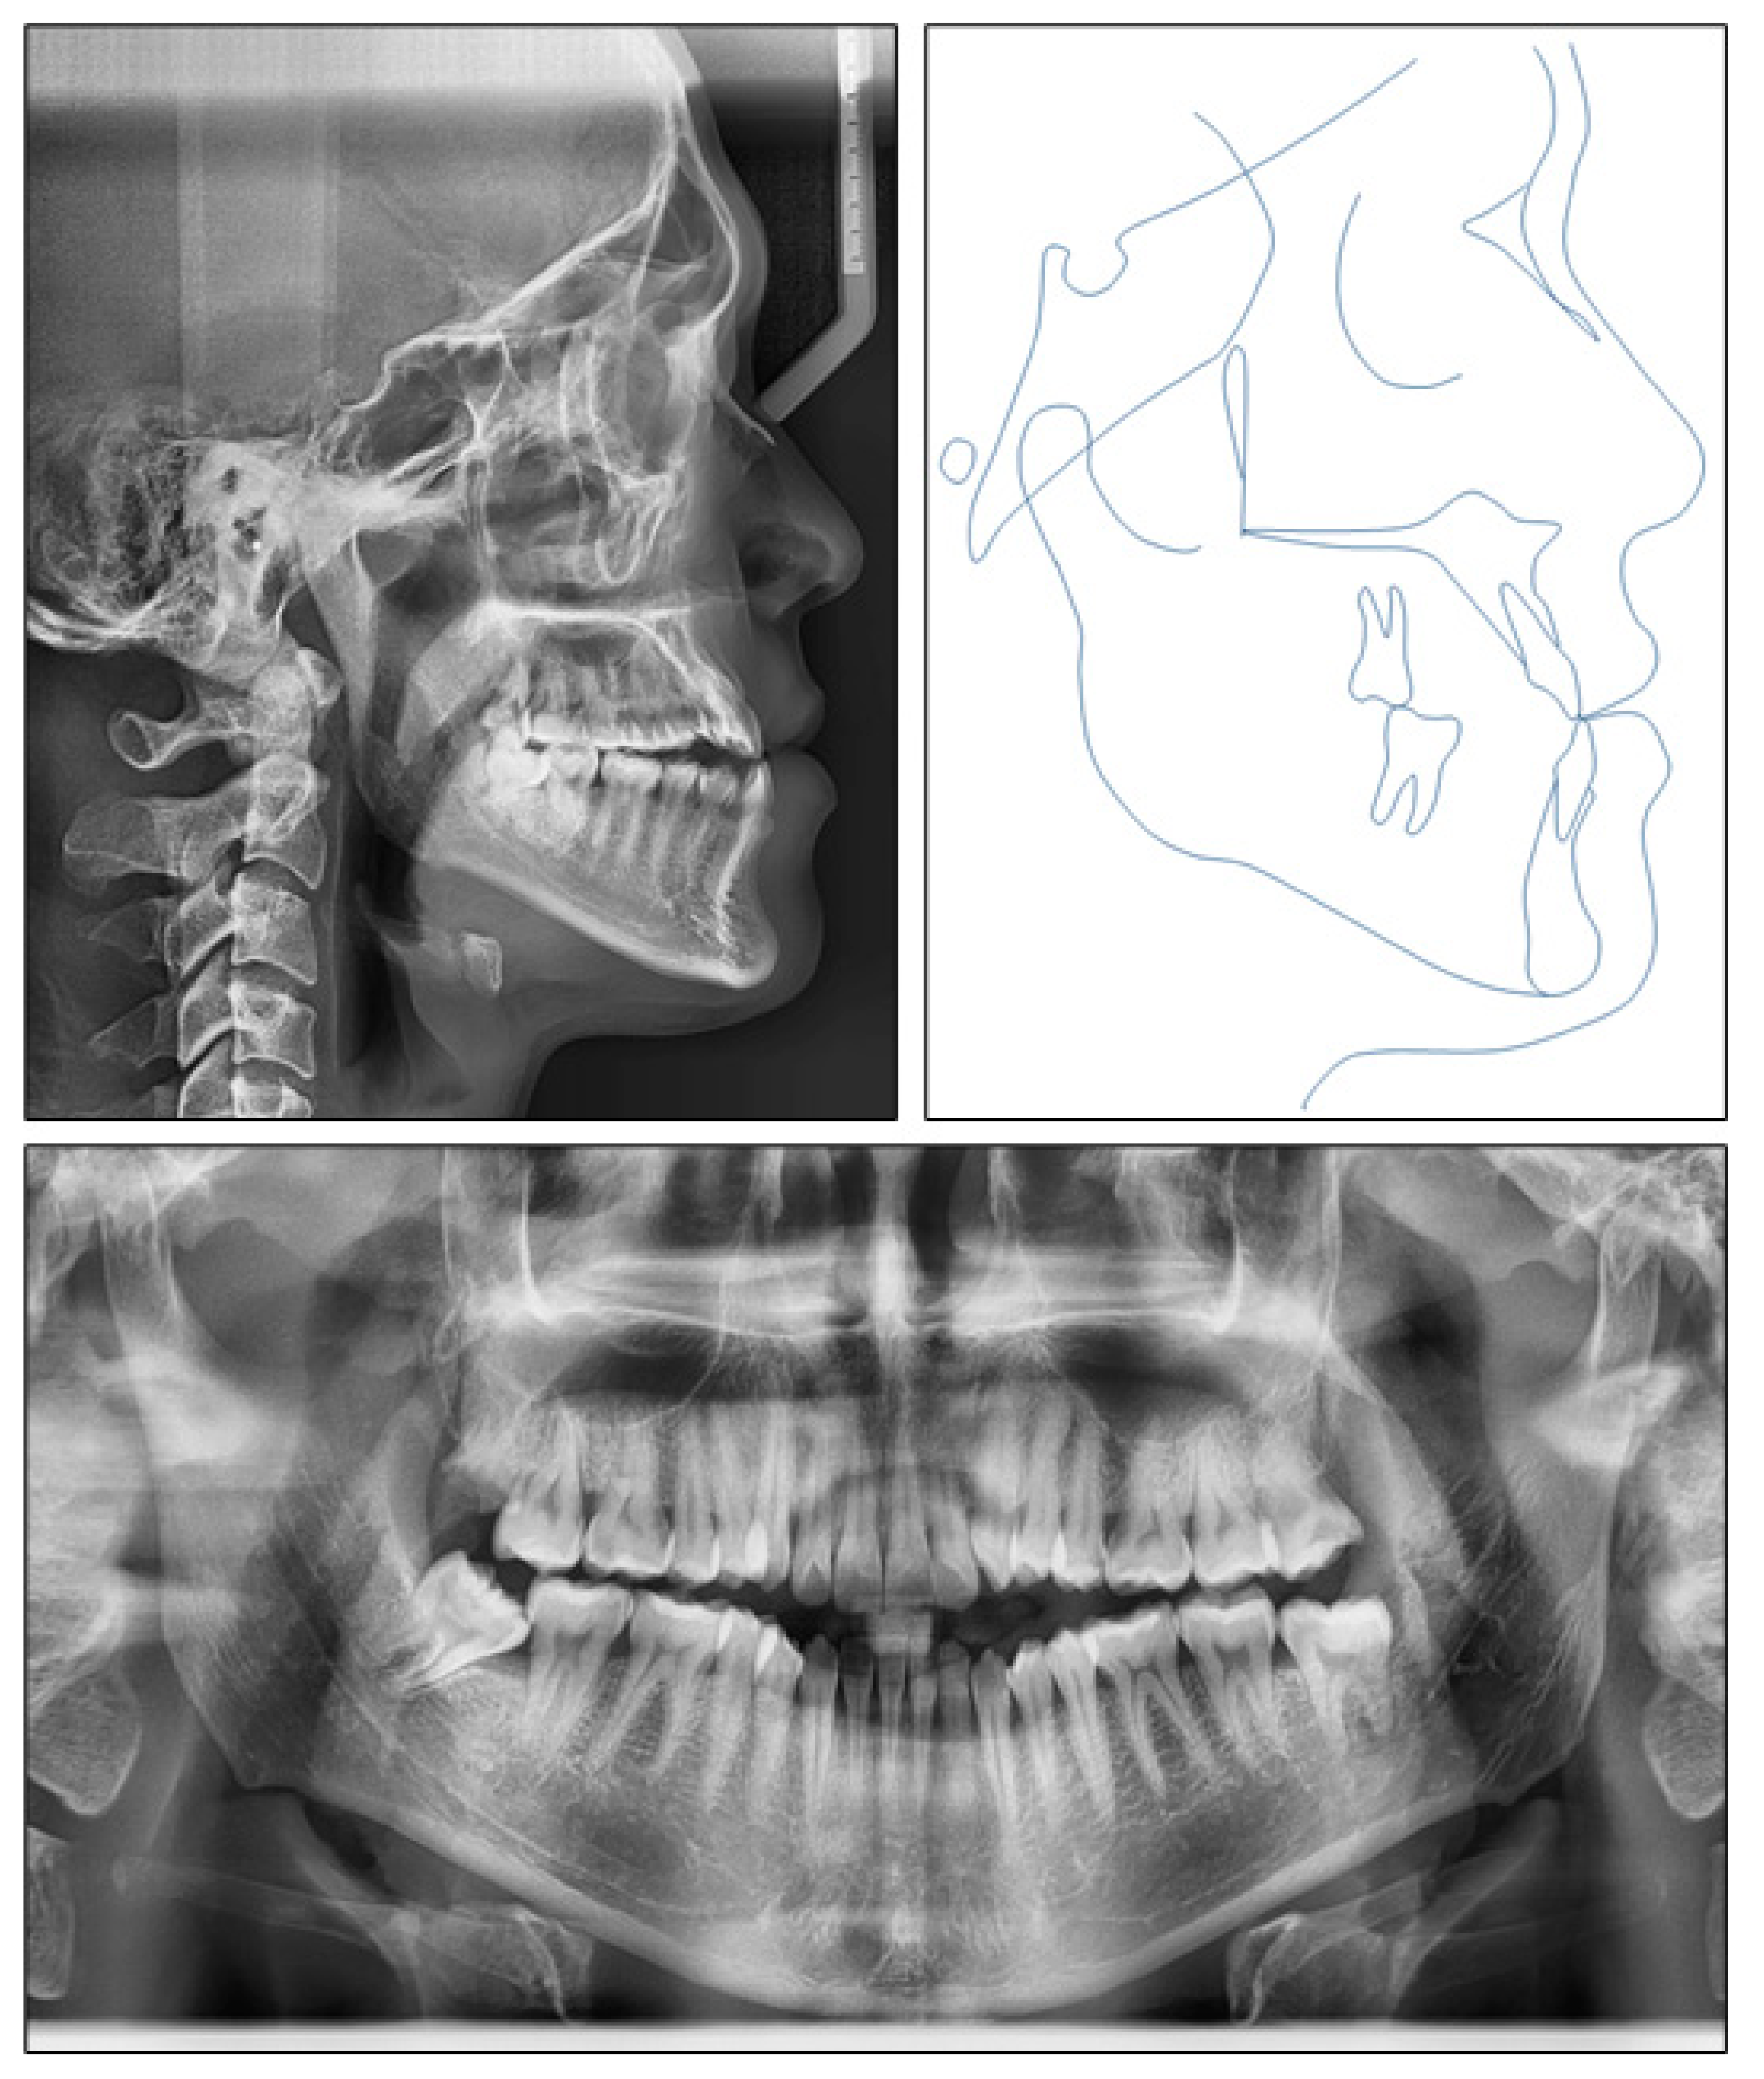

Skeletal Class III Malocclusion with Lateral Open Bite and Facial Asymmetry Treated with Asymmetric Lower Molar Extraction and Lingual Appliance: A Case Report

2.1. Diagnosis and Etiology